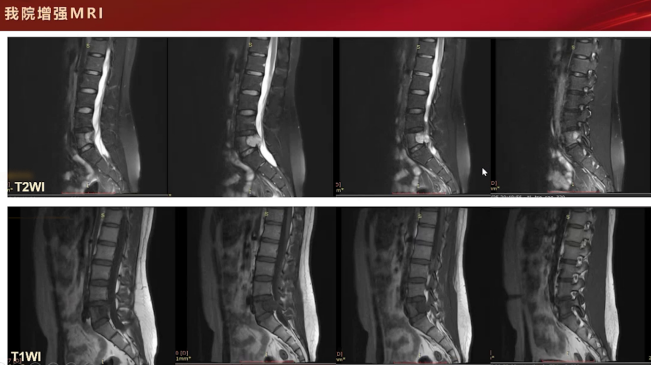

随后的磁共振检查,T2加权像呈高信号,增强扫描可见分隔样环形轻中度强化,这些支持征象提示为软骨源性肿瘤。主要依据包括T2信号较高、膨胀性骨质破坏伴硬化边、内部点状钙化以及增强扫描呈环形和分隔样强化,综合判断为软骨肉瘤。